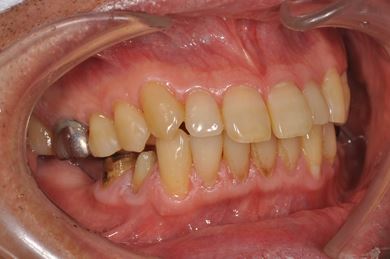

| 性別/年齢 | 男性 / 57歳 | ||||||||||||||||||||||||||||||||

| 主訴 | 右奥歯のブリッジが取れ、支柱の2本の歯が痛むため、インプラント治療を希望。 | ||||||||||||||||||||||||||||||||

| 治療内容 | インプラント2本、ハイブリッドセラミック2本 | ||||||||||||||||||||||||||||||||